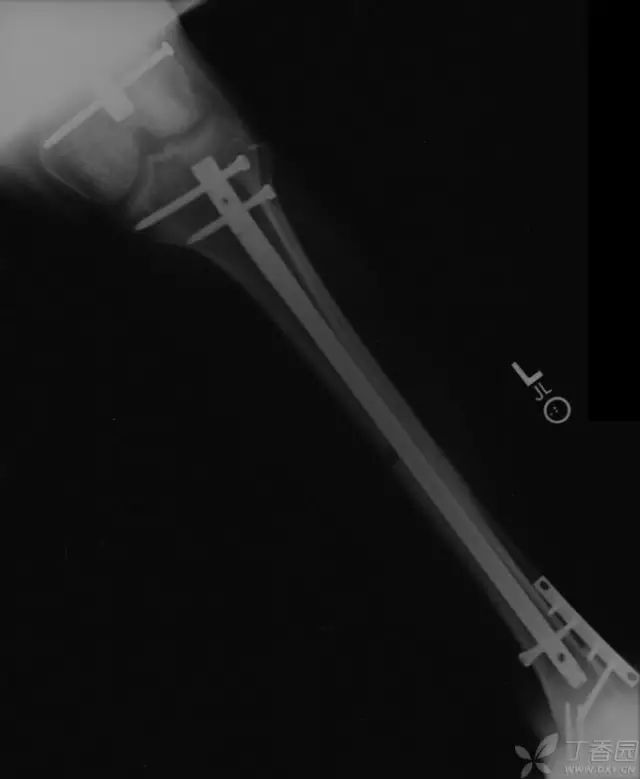

病例三

胫骨远端开放性骨折,远端骨折块游离在体外

游离骨块浸泡在抗生药物生理盐水溶液中

X 线片可见骨块寄养在自体下腹部皮下

创口清创、大量冲洗以后一期外固定支架固定,缺损区域抗生素骨水泥填充

二期回植,更换为钢板内固定

回植后 8 个月,骨折无感染迹象